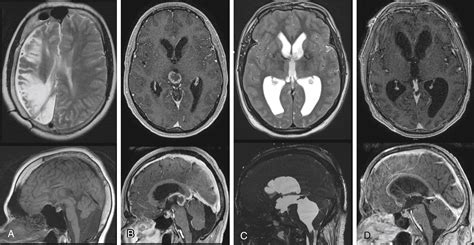

To confirm a diagnosis, physicians rely on a combination of clinical evaluation and advanced imaging technology. Because hydrocephalus in adults shares symptoms with conditions like Alzheimer’s or Parkinson’s, accurate diagnosis is the first priority.

MRI (Magnetic Resonance Imaging) Provides detailed images of the brain to visualize ventricle size.

CT Scan Quickly identifies enlarged ventricles and potential obstructions.